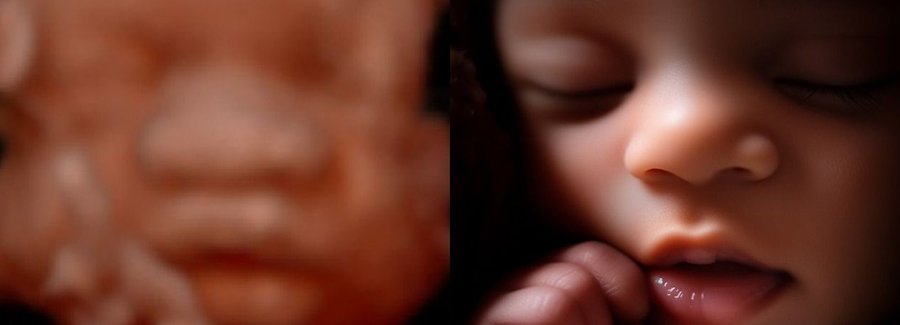

Often referred to as 5D, HD or FRV (fetal realistic view), 5D/HD is the newest development in pregnancy imaging. It captures and combines high definition volume data to create automated images with amazing color and clarity so you can see your baby as though you were looking from inside the womb.